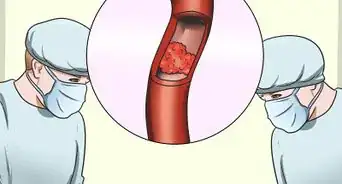

Your blood carries oxygen and important nutrients throughout your body, so it's really important to have a steady, healthy level of blood flow to your brain. In fact, decreased blood flow to your brain is associated with a number of health concerns, including an increased risk of dementia, depression, and stroke. Fortunately, it's actually possible to improve your circulation and increase blood flow for a healthier brain. This article will walk you through a variety of simple lifestyle changes that can help.